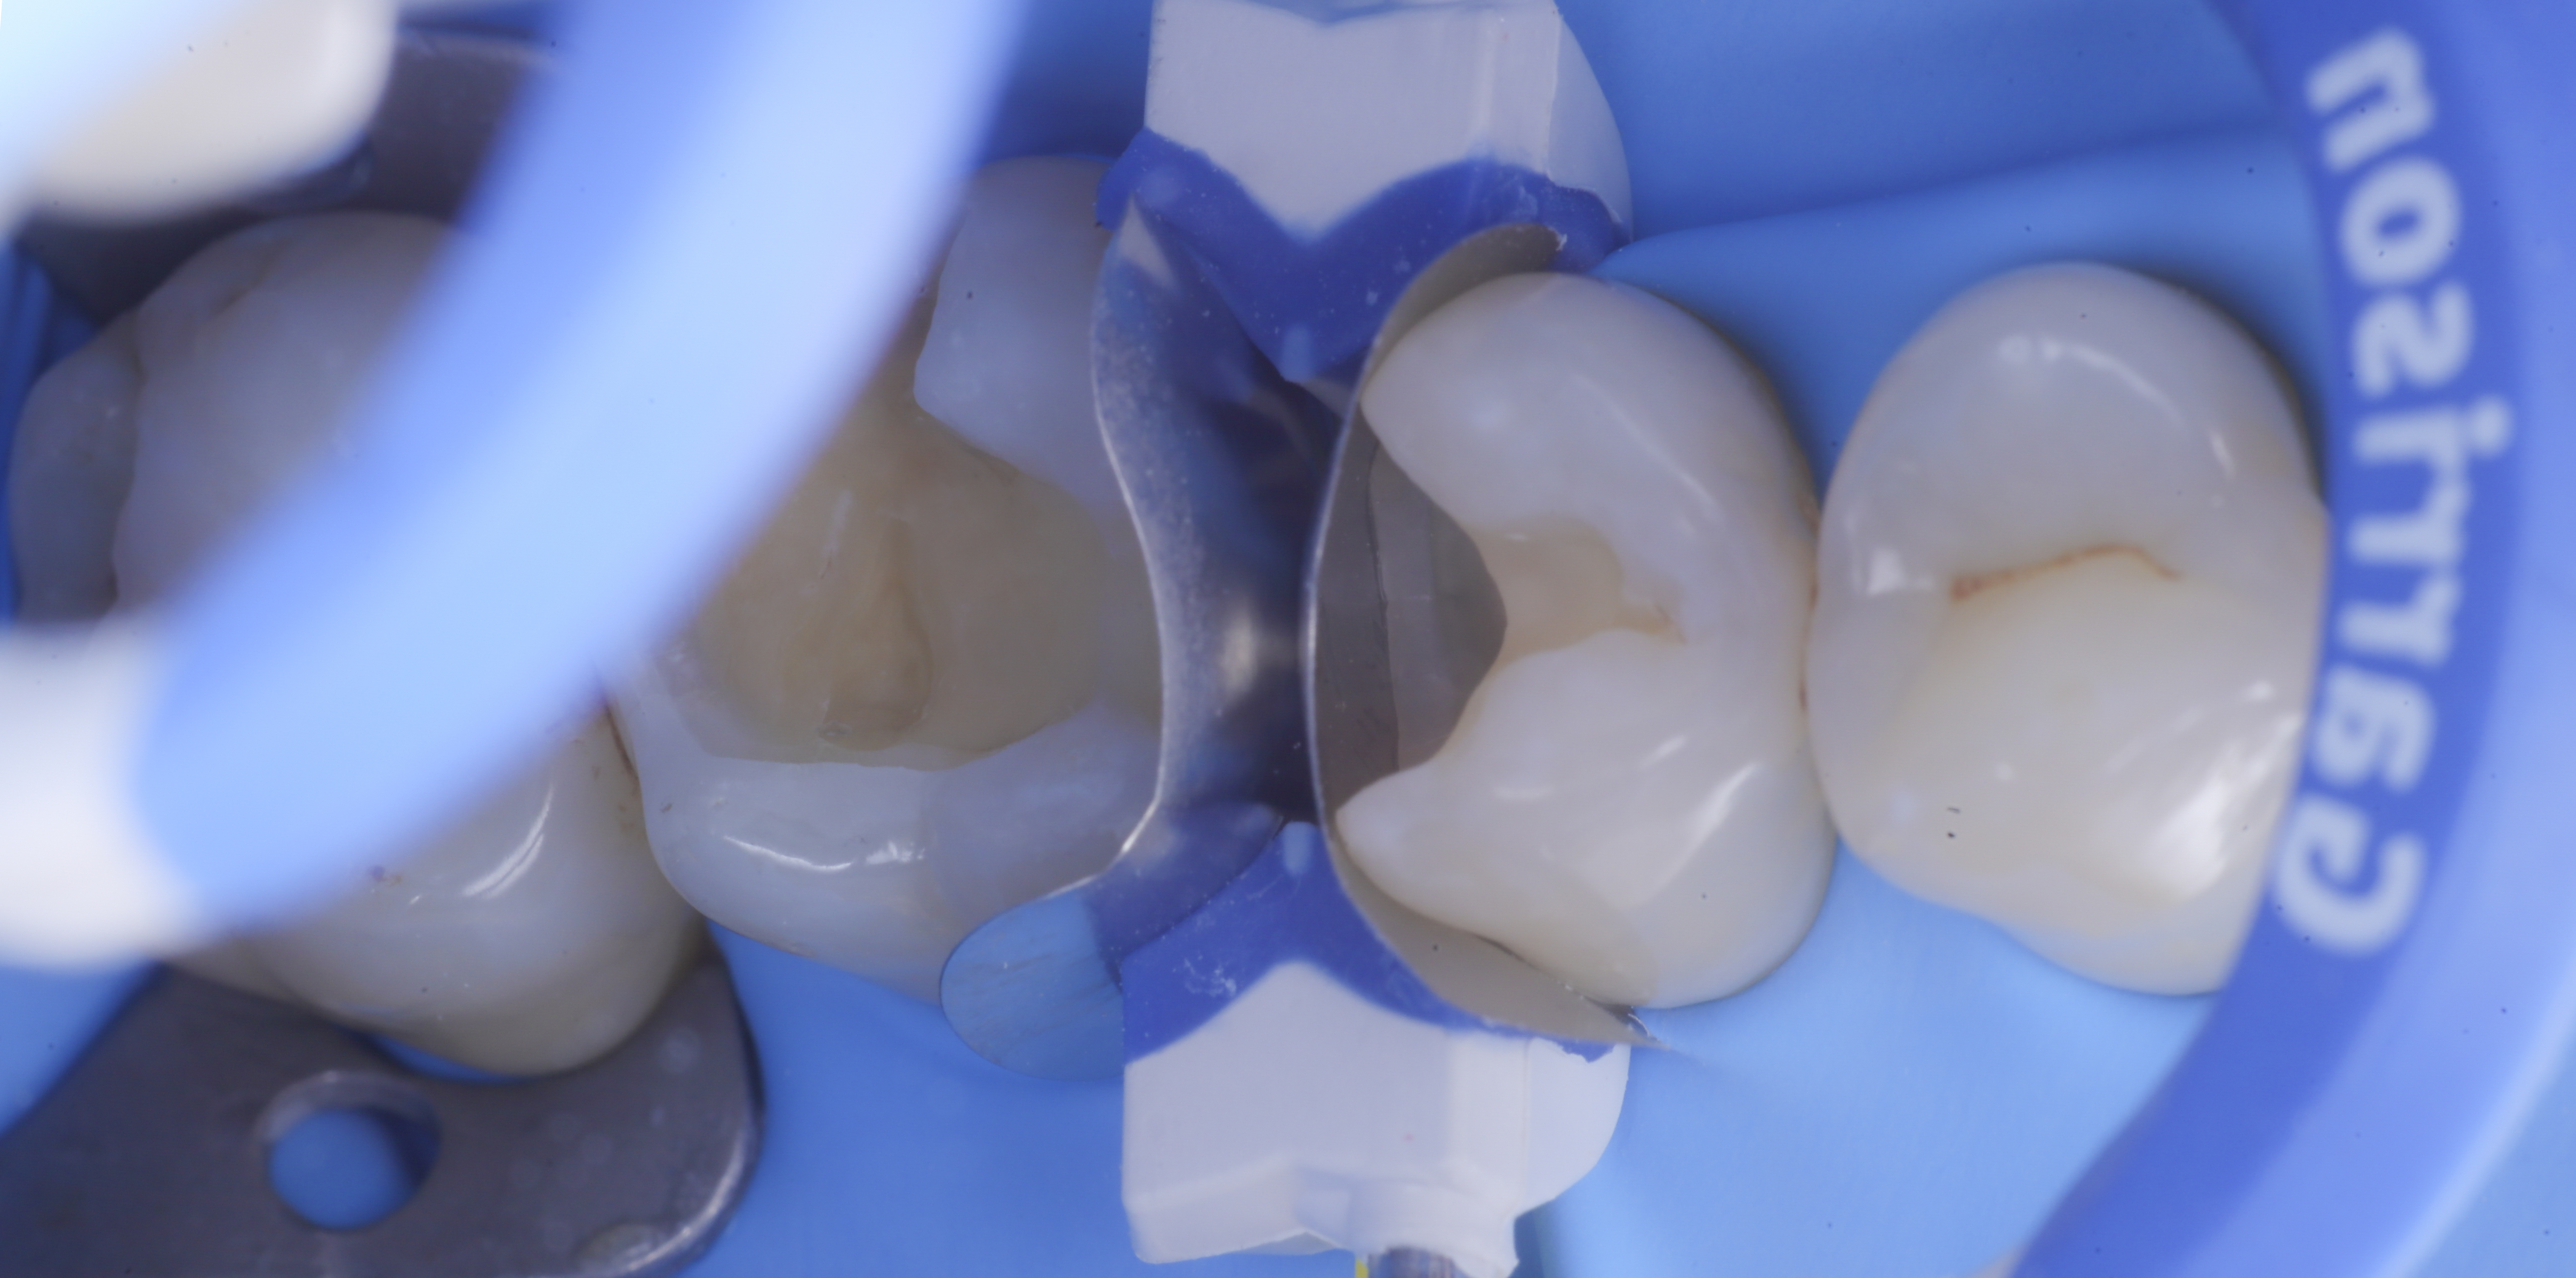

foto 3 Aspetto vestibolare della cavità ultimate

foto 7 Aspetto vestibolare delle pareti interprossimali appena create